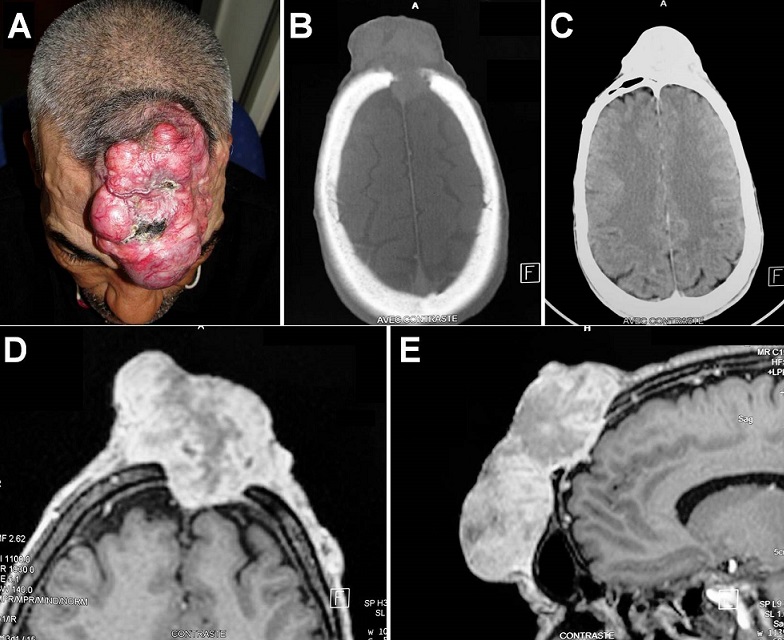

A 53-year-old man, previously healthy, presented with a slow-progressive enlarging mass in the midfrontal area which had developed 14 years previously without headache. On physical examination, this nodular reddish mass (11 x 7 x 5 cm) was fluctuant to pressure and tethered to the underlying frontal bone (A). There was no neurological deficit and no superficial lymph nodes. Cranial computed tomography scan showed an irregular median calvarial defect with poorly bony defined margins and left frontal sinus invasion (B-C). Magnetic resonance imaging revealed intracranial extension of the tumour which invaded the dura and the superior longitudinal sinus (D-E). Local biopsy was performed and histological study consisted with a dermatofibrosarcoma. In this specific case, radiotherapy was planned before surgical excision and craniofacial reconstruction. Dermatofibrosarcoma is a slow-growing mesenchymatous tumour of the skin with high local malignancy and great opportunity of recurrence. It usually occurs in the trunk or extremities. In the majority of cases the tumour remains asymptomatic for a long time. Head (scalp) and maxillofacial involvement is rare particularly with skull vault and intracranial extension. To improve local control after surgery, wide excision is recommended but difficult in significant anatomic region as in our case.